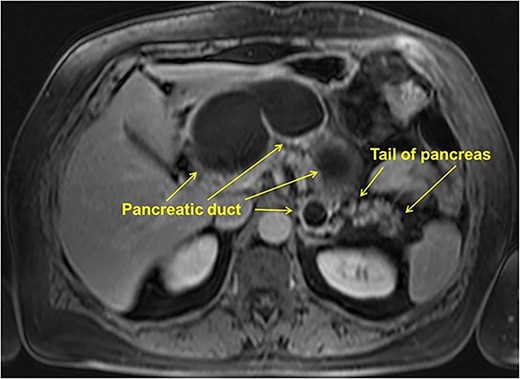

MRI showed cystic lesion in the pancreatic head, neck, and body, connected with the MPD, the maximum diameter of 75 mm, with the parenchyma only in the pancreatic tail (Fig. 2).